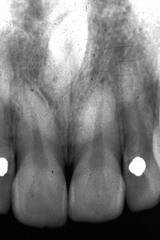

radicular cyst

-asymptomatic radiolucency associated with the root of a NONVITAL tooth